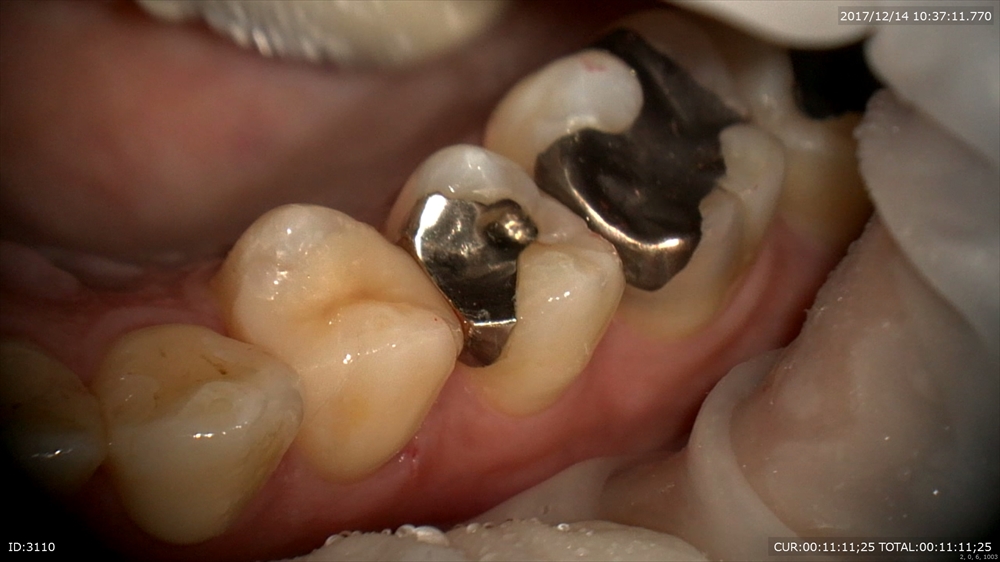

では証拠に本日の虫歯の治療の御紹介

一見健康に見える銀歯(一番手前)

歯科ドックで内部虫歯が発覚!こんなに大きく神経に近い。マイクロスコープで丁寧に。